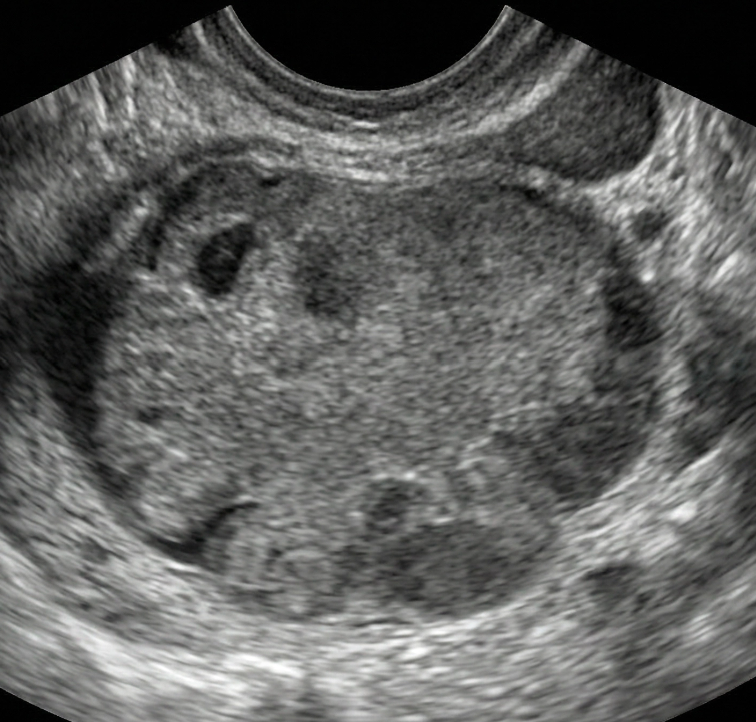

O-RADS US 4 — Risco Intermediário

Risco: 10-<50%Cisto multilocular sem componente sólido ≥ 10 cm ou com IC = 4, cisto unilocular/multilocular com componente sólido, lesão sólida com superfície lisa e IC = 2–3.

Cisto multilocular com componente sólido